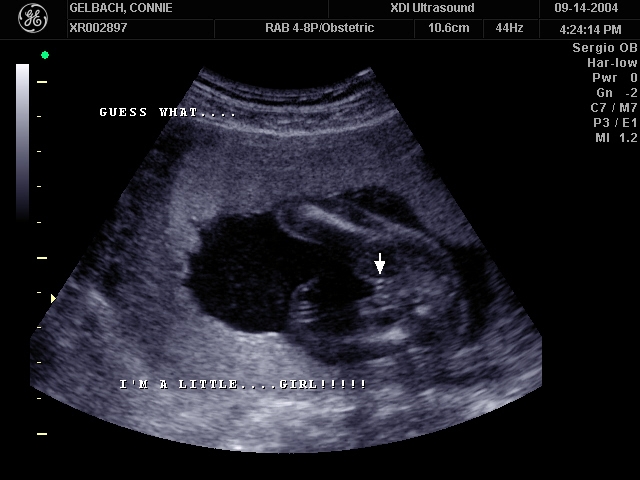

Sonograms